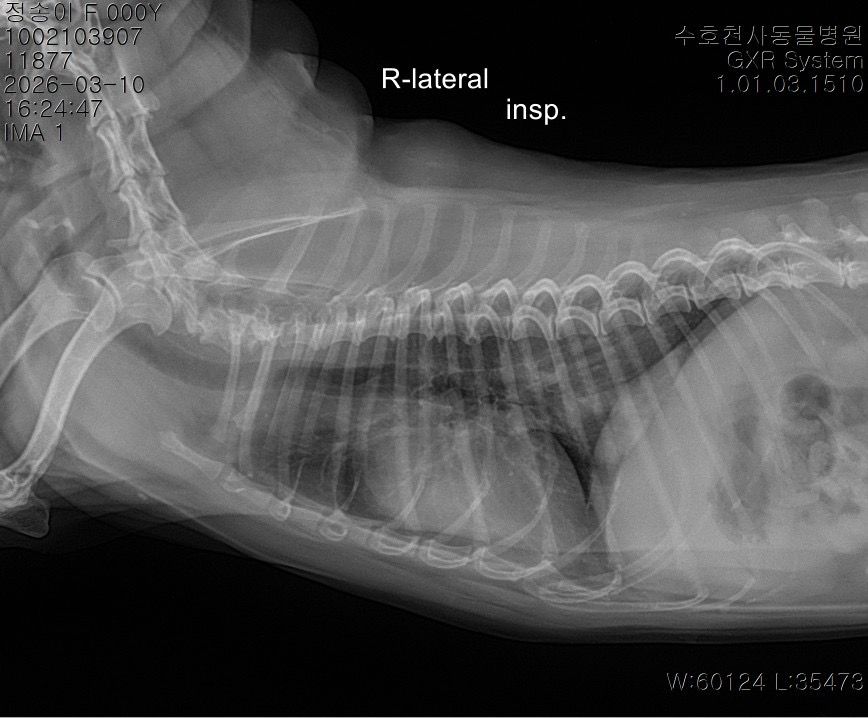

말씀주신 것처럼 보여주신 방사선에서 흉강 내 종양 (폐, 흉강 등)이 의심되는 상황입니다. 다만 방사선 사진만으로는 종양 여부와 정확한 위치, 개수, 성격을 완전히 판단하기 어렵고 CT 촬영을 통해 정확한 판단이 이루어져야 수술 여부 등을 결정할 수 있습니다. 좌측 폐는 앞엽과 뒷엽으로 나눠지긴 하고, 사진 상으로는 좌측 뒷엽 혹은 오른쪽 폐와 왼쪽 폐 사이에 있는 덧엽 부분에도 종괴가 위치하는 것으로 보이지만, 방사선으로는 어느 폐엽에서 발생한 것인지 정확히 구분할 수는 없습니다.

종괴가 단일 병변인지 여러 개인지, 정확히 어느 폐엽에서 시작되었는지, 주변 조직이나 다른 폐엽으로 이어져 있는지,

원발성 종양인지 전이성 병변인지 등을 알려면 CT 촬영이 필요하며 치료 방향도 CT 결과에 따라 달라집니다. 만약 한 두개의 폐엽에 국한된 단일 종괴라면 경우에 따라 해당 폐엽을 제거하는 수술을 고려하는 경우가 있습니다. 하지만 주변 조직으로의 침습, 원격전이 혹은 너무 많은 엽을 포함하고 있어 수술 후 호흡 합병증이 예상되는 경우 수술로 완치 기대는 어렵습니다. 빠른 CT 촬영을 추천드립니다.

사진상으로는 상당히 전형적인 원발성 폐종양의 방사선 양상이지만 말씀 하신 "방사선 엑스레이 촬영 한 것을 통해서서도

폐 종양인지 아닌지, 갯수를 확인가능한지

한 폐엽에만 있는 상황인건지 아니면 윗쪽 중간 폐엽과도 이어져있는지 원발성,악성 등등"에 해당하는 내용은 방사선 사진으로 평가하는게 아닌 흉부 CT검사로 확인해야 하는 사항들입니다. 흉부 방사선 검사는 저렴하지만 정확도와 세밀한 내용 평가에 제한이 있습니다. 우선 주치의와 상의하시고 흉부 CT검사를 촬영 한 후에 침습이나 전이 여부 평가하고 수술 계획 잡으시기 바랍니다. 원발성 폐종양인 경우 악성이더라도 수술로도 완치가 가능한 몇 안되는 질환이니 수술을 빨리 하면 할 수록 좋을 수 있으니 아이에게 주워진 시간을 아끼시기 바랍니다.